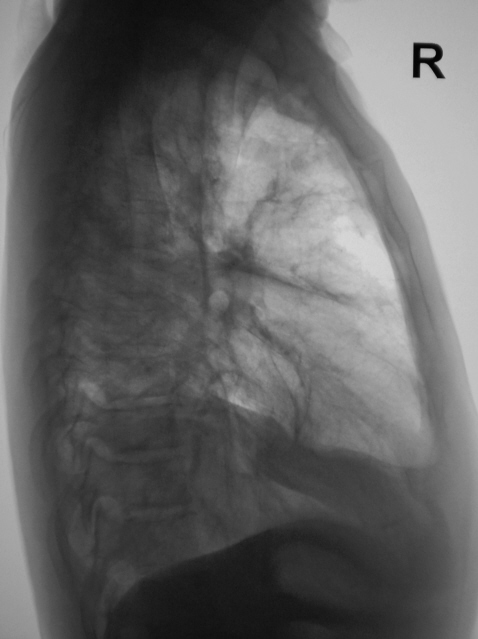

На рентгенограммах, произведенных в прямой и правой боковой проекциях, получена такая скиалогическая картина.

Возникла мысть по поводу осумкованного паракостального и интерлобарного плеврита. Решено провести линейную томографию в прямой проекции.

После проведенного исследования мысль - об осумкованном паракостальном и  интерлобарном плеврите. Ваше мнение коллеги?

Все стало хуже, а оттого понятней. По первой серии писал: "Если больной острый, да к тому же южанин, я бы, акцентировав внимание на плевральный компонент (отграниченный плевральный выпот?), отправил на консультацию в ПТД. У такого пациента и эмпиема может быть.." Теперь в ПТД посылать уже не надо, а сразу пунктировать и лечить, желательно в торакальном отделении.

При динамическом рентгеновском наблюдении определяется изменение конфигурации тенеобразования в нижне-наружних отделах справа, сливающиеся с куполом диафрагмы. Но на этом фоне обращает внимание сближение ребер правой половины грудной клетки, а также сохраняется впечатление объемного уменьшения правого легкого. При этом тень средостения частично смещена влево, а просвет трахеи занимает срединное положение. Складывается впечатление сохранение просветов бронхов. Все это заставляет думать о длительном течении гидроторакса справа, вероятно осложненного воспалительным процессом,  с формированием выраженных фиброзных изменений, вызывающих уменьшение объема правого легкого.